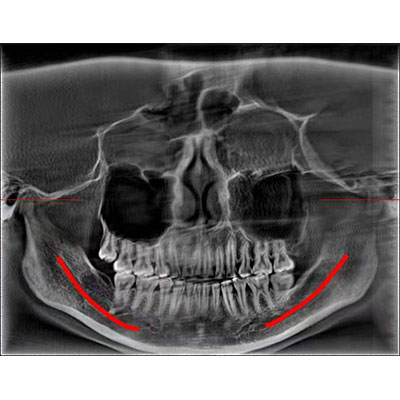

通過三維容積影像,提取高清口腔全景影像。

專有圖像校正技術,去除金屬偽影,提高圖像分辨率。